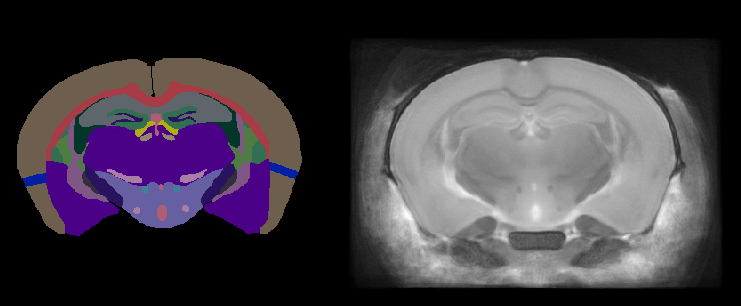

Figure 1. Two-dimensional view of the Dorr mouse MRI brain atlas: annotations (left) and reference (right).

The atlas was constructed from within-skull, T2-weighted MR images acquired at 32 μm isotropic resolution from forty 12-week-old mice scanned at 7T. Following normalisation, registration, and averaging of individual scans, 62 distinct brain structures were manually delineated.